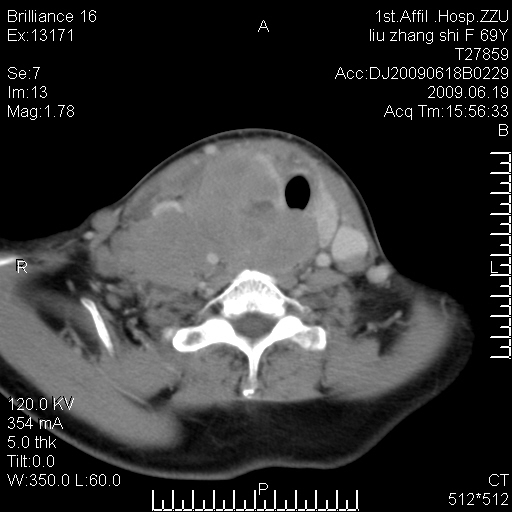

标题: CT26782:女,69岁,颈部占位,3天后公布病理结果。

【病理证实系列】女,69岁,颈部占位,有病理结果,3天后公布。(由于病例时间较久,临床资料不全,请网友见谅)本系列将有几百种常见、少见及罕见病例,均经病理证实。病例资料来自郑州大学第一附属医院。与网友共享,本人有空就发。

甲状腺癌并颈部淋巴结转移。感谢楼主的良苦用心,谢谢。

甲状腺癌并颈部淋巴结转移。

需与鼻咽癌鉴别!

支持甲状腺癌广泛侵及周围结构并颈部淋巴结转移。

鉴别:淋巴瘤、恶性神经源性病变、恶性纤维组织细胞瘤。

病理结果:颈部非霍奇金淋巴瘤。